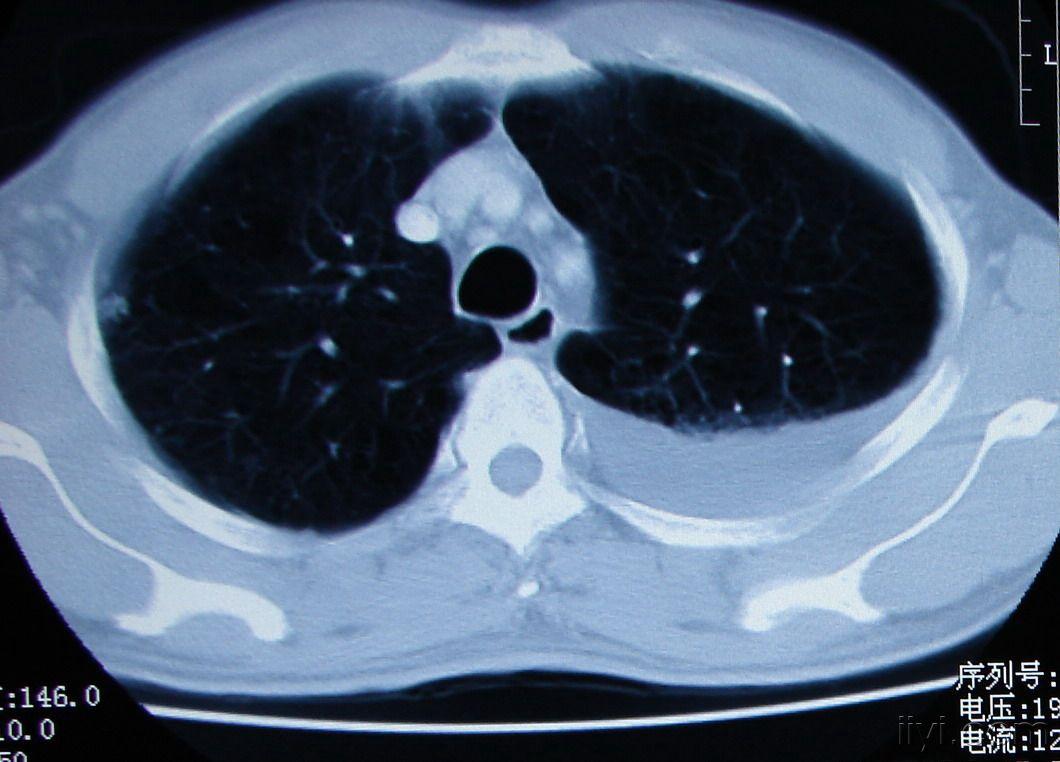

吸烟导致双肺坠积效应先来看一下正常人的胸部ct:胸廓的横径和前后径